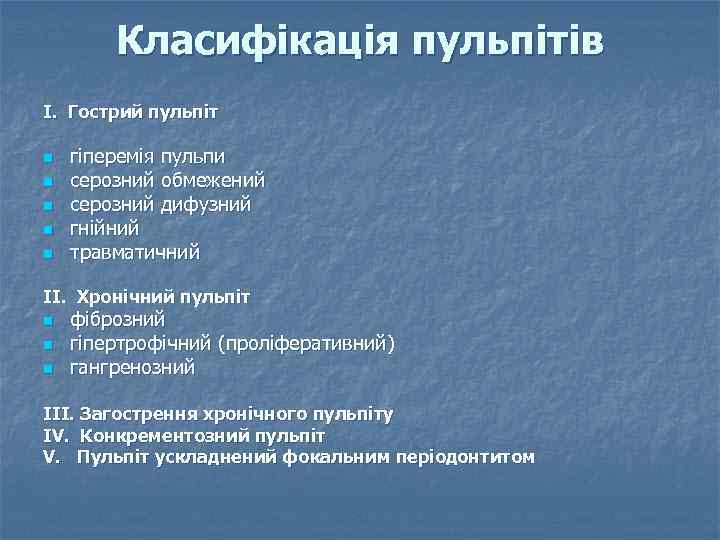

Класифікація пульпітів І. Гострий пульпіт n n n гіперемія пульпи серозний обмежений серозний дифузний гнійний травматичний ІІ. Хронічний пульпіт n n n фіброзний гіпертрофічний (проліферативний) гангренозний ІІІ. Загострення хронічного пульпіту ІV. Конкрементозний пульпіт V. Пульпіт ускладнений фокальним періодонтитом

Класифікація пульпітів І. Гострий пульпіт n n n гіперемія пульпи серозний обмежений серозний дифузний гнійний травматичний ІІ. Хронічний пульпіт n n n фіброзний гіпертрофічний (проліферативний) гангренозний ІІІ. Загострення хронічного пульпіту ІV. Конкрементозний пульпіт V. Пульпіт ускладнений фокальним періодонтитом